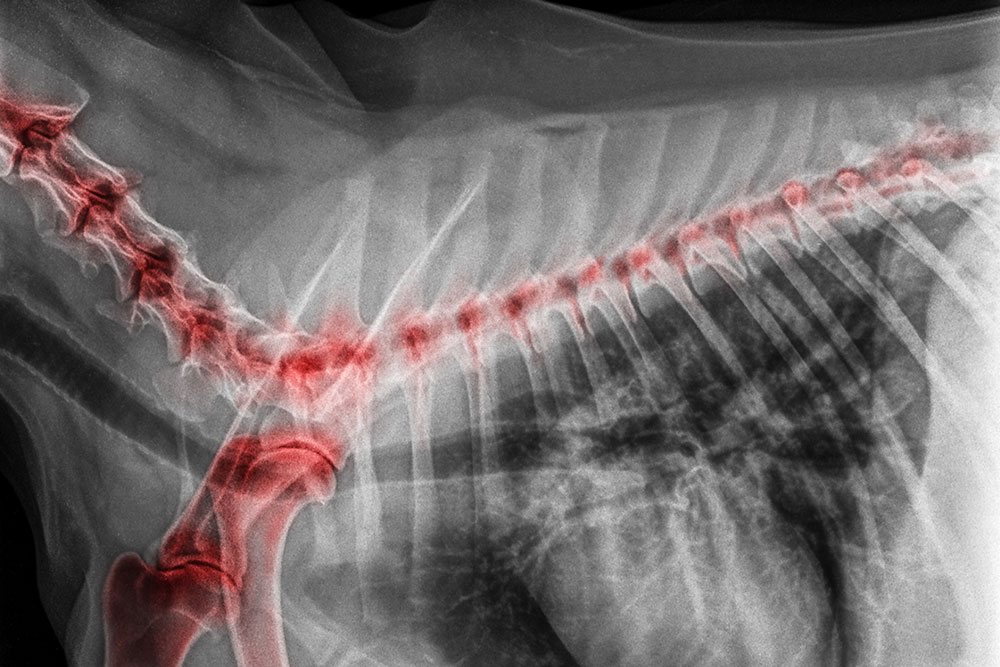

Wobblers Syndrome, also called cervical spondylomyelopathy, is a condition where structures in the neck compress the spinal cord and cause weakness and an unsteady gait. You might notice your dog walking with a wider stance than usual, knuckling their paws, or scuffing their nails on the ground. It can look like they are having trouble figuring out where their feet are.

CT and MRI provide detailed views of bones, discs, and the spinal cord that are far superior to routine X-rays for compression problems. CT is especially useful for identifying bony changes like those seen in wobblers, while MRI excels at showing soft tissue details like disc material and the spinal cord itself.